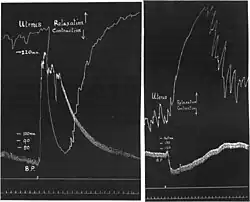

Research on the catecholamines was interwoven with research on their receptors. In 1904, Dale became head of the Wellcome Physiological Research Laboratory in London and started research on ergot extracts. The relevance of his communication in 1906[70] "On some physiological actions of ergot" lies less in the effects of the extracts given alone than in their interaction with adrenaline: they reversed the normal pressor effect of adrenaline to a depressor effect and the normal contraction effect on the early-pregnant cat's uterus to relaxation: adrenaline reversal. The pressor and uterine contraction effects of pituitary extracts, in contrast, remained unchanged, as did the effects of adrenaline on the heart and effects of parasympathetic nerve stimulation. Dale clearly saw the specificity of the "paralytic" (antagonist) effect of ergot for "the so-called myoneural junctions connected with the true sympathetic or thoracic-lumbar division of the autonomic nervous system"—the adrenoceptors. He also saw its specificity for the "myoneural junctions" mediating smooth muscle contraction as opposed to those mediating smooth muscle relaxation. But there he stopped. He did not conceive any close relationship between the smooth muscle-inhibitory and the cardiac sites of action of catecholamines.

Adrenaline reversal after Henry Hallett Dale (1906). An ergot extract was injected between left-hand and right-hand tracings.

Adrenaline reversal after Henry Hallett Dale (1906). An ergot extract was injected between left-hand and right-hand tracings. -